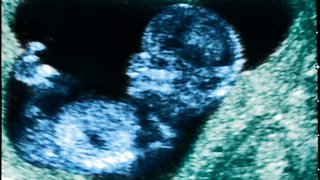

A Cardiff woman who was wrongly told that she'd had a miscarriage

"I couldn't look at pictures" of my baby, says 20-year-old new mum Katie.